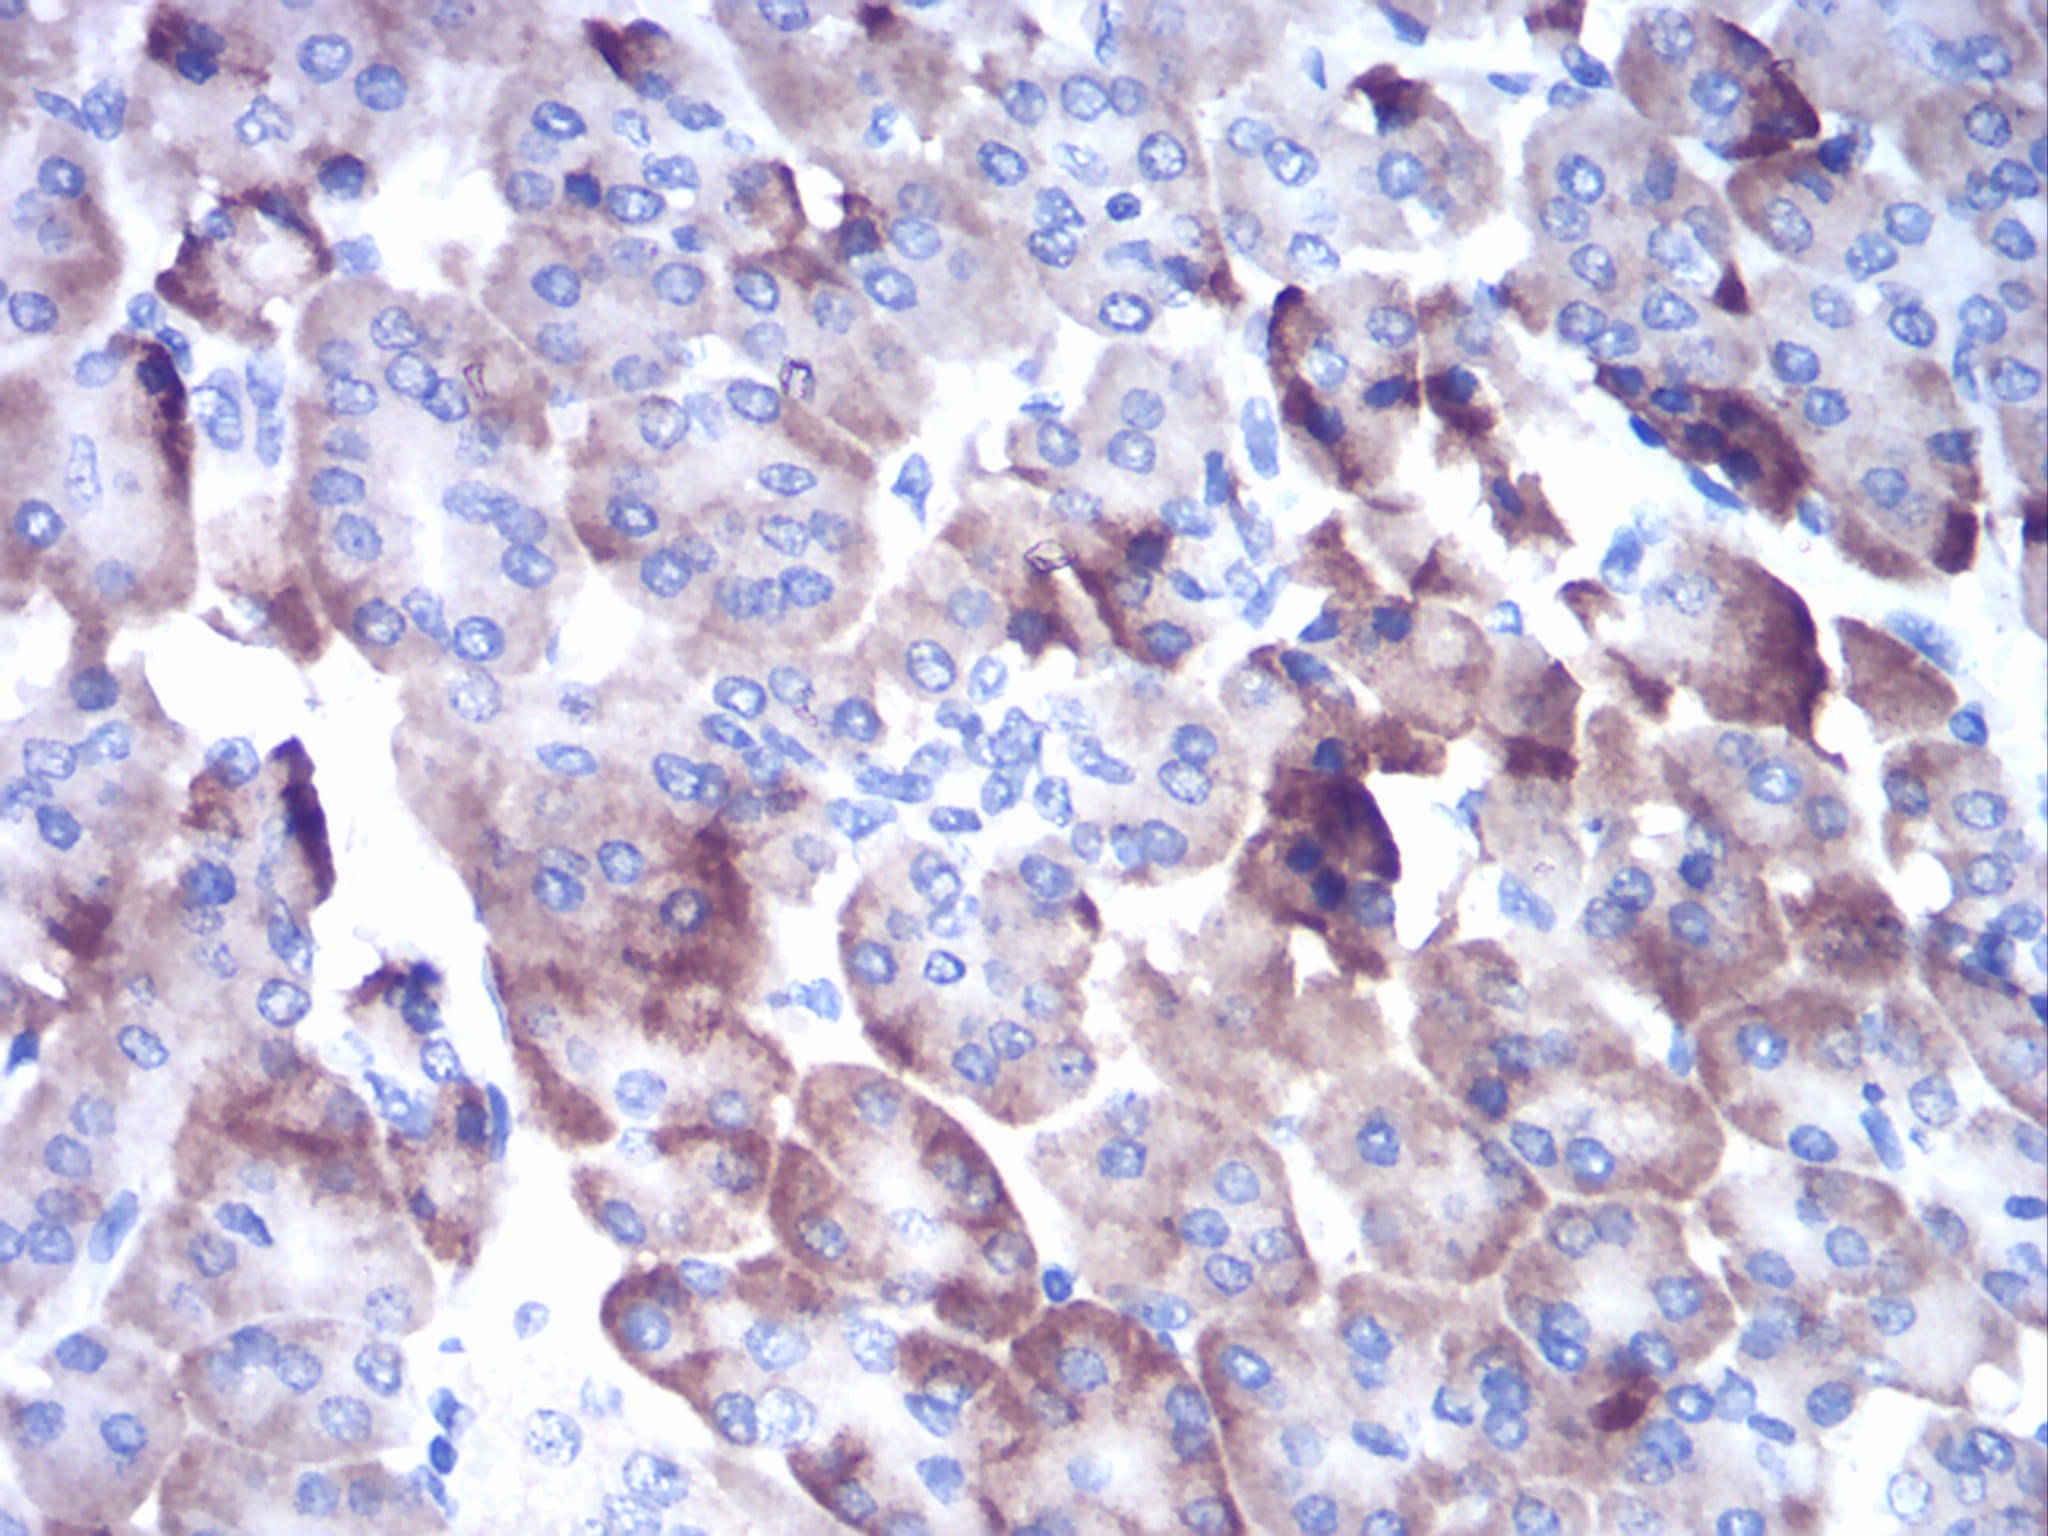

- Immunohistochemical analysis of paraffin-embedded human pancreas tissues using CTSD mouse mAb with DAB staining.